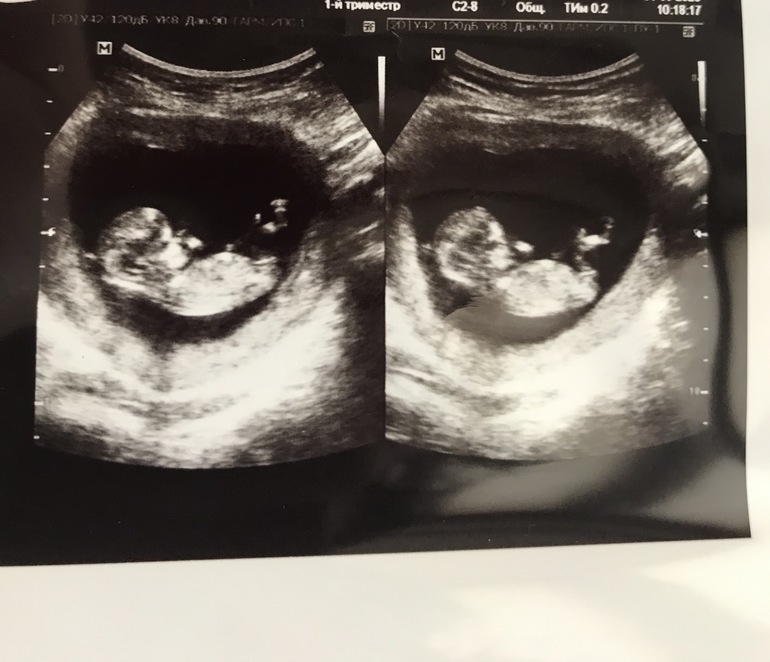

На первом узи даже не предположили пол, кто разбирается, кого видите? Скоро на второе уже Узи, но очень интересно

Мальчик или девочка?

По аккуратному строению и по половому бугорку смело предполагаю что это девчулечка 👸🎀💗

Подтвердили мне ДЕВОЧКУ на узи в 16 недель и не поверив сделала анализ в инвитро😅

И пол плода-женский🥳

Как понять по такому снимку? 😁 Тут только на ромашке гадать)

А это мой мальчик на сроке 12 недель в 2016 году, тогда предположили девочку на первом узи, а потом оказался мальчик 🤷♀️